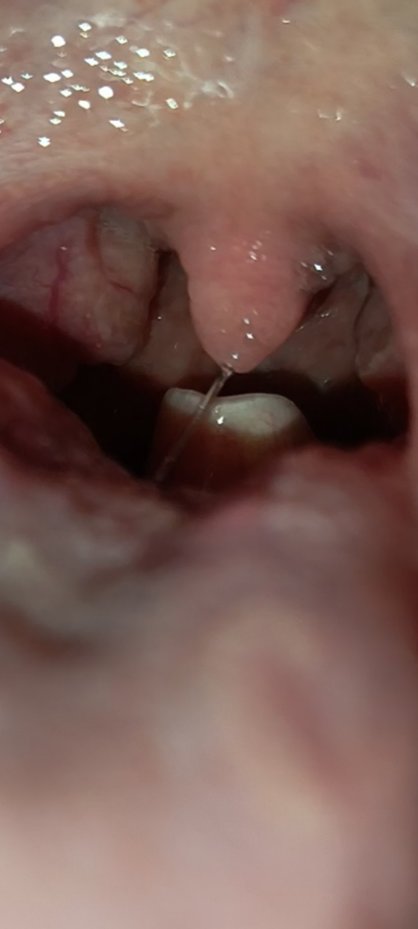

niektorym detom /ludom vidiet epiglotis aj fyziologicky, prosim nestraste sa tu. /som pediater/. Pokial samozrejme nie je dieta dychavicne, neslini, nesedi v predklone, tak to nie je epiglotitida. obzvlast ak je riadne ockovane.

ja som myslela, že sa pýta na to biele, čo je úplne vzadu a vyzerá to ako zub

@amdornik to je epiglotis

@arabesqe niektorým je to vidieť viac, iným menej, ale to ma každý človek.

@anonym_ce941f život ohrozujúce by bolo ho nemať

@arabesqe Ako je pisane vyssie, pokial dieta len kasle a nema ine tazkosti, je to ok, to belave vzadu je epiglottis, teda prichlopka, teda normalna cast ludskeho tela v krku, je to podobna fotka, akoby niekto odfotil jazyk a riesil, ze ma odfotene nieco, teda jazyk.., a ci s tym jazykom na fotke ma utekat na pohotovost... Som tiez lekar...